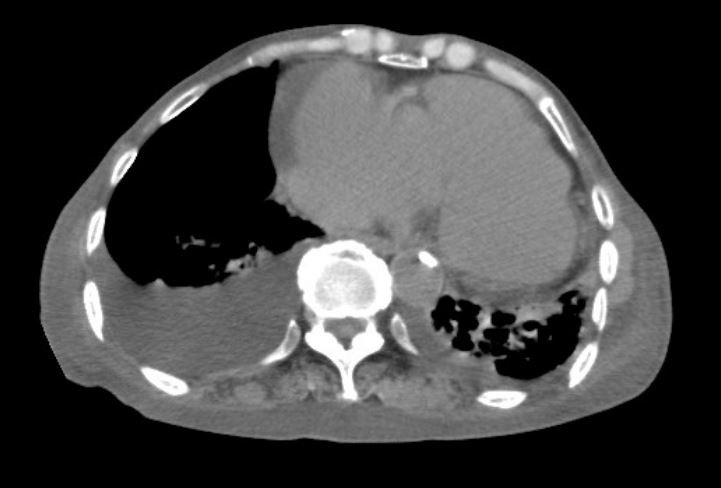

心影增大和胸腔积液

▶ 胸部X光或CT:评估心肺影像变化。